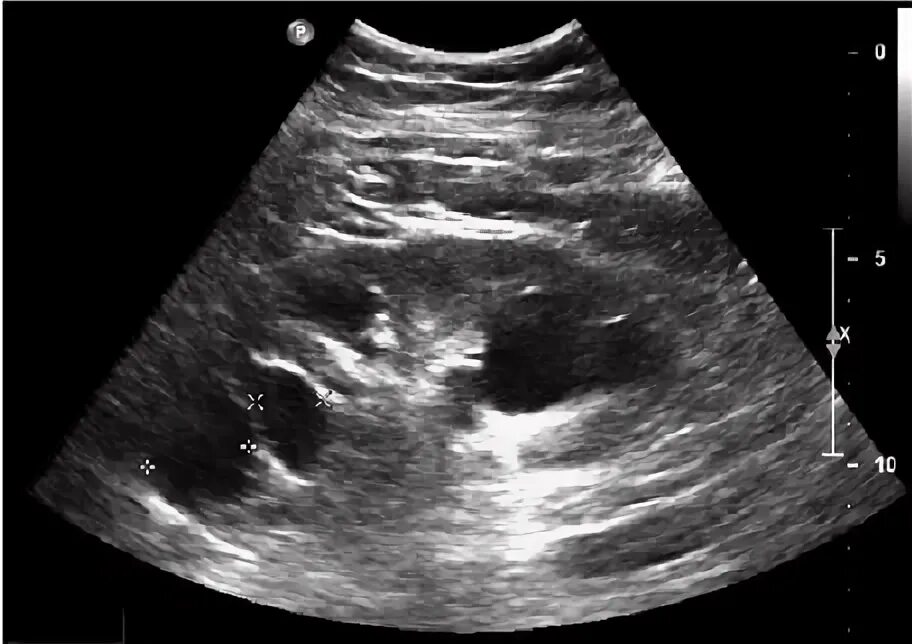

Узи надпочечников и забрюшинного пространства подготовка